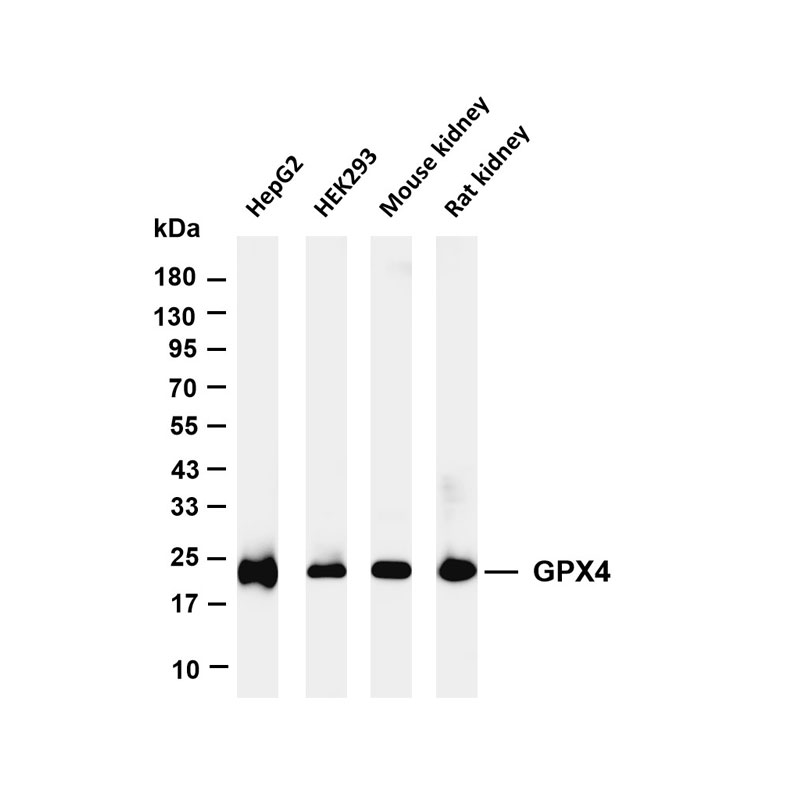

(VII) Issues Related to Primary Antibody Selection and Incubation

The selection of primary antibody is critical for achieving specific staining and reliable conclusions, and it should follow the principles of "high specificity, high sensitivity, low background, stable results, and good reproducibility."

Core Issues and Analysis:

1 Antibody Specificity: The specificity of an antibody is reflected in three aspects: tissue specificity, cellular specificity, and subcellular localization specificity.